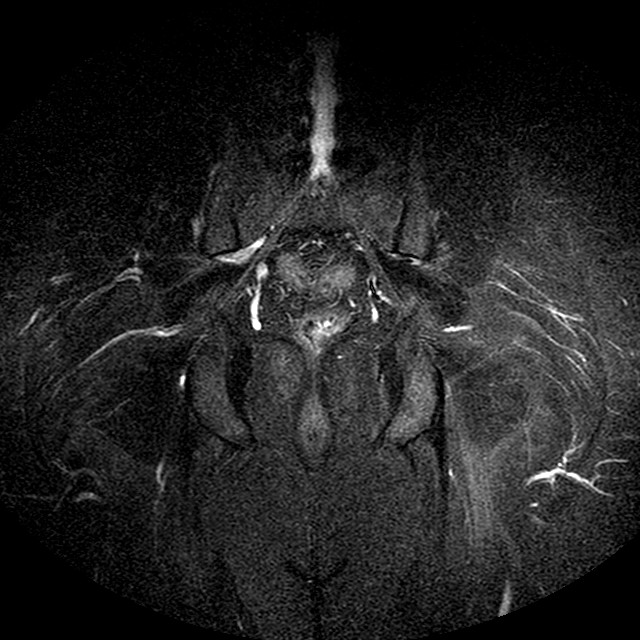

Esami: RMN BACINO

STIR

Evidenti e simmetriche alterazioni osteofitosiche in regione coxo femorale con riduzione delle rime articolari. Degenerazione completa del cercine glenoideo. Non attuali segni di versamento articolare. Non segni di edema osseo che escludono attuale algodistrofia od osteonecrosi. Lieve e simmetrica riduzione del trofismo della muscolatura glutea.